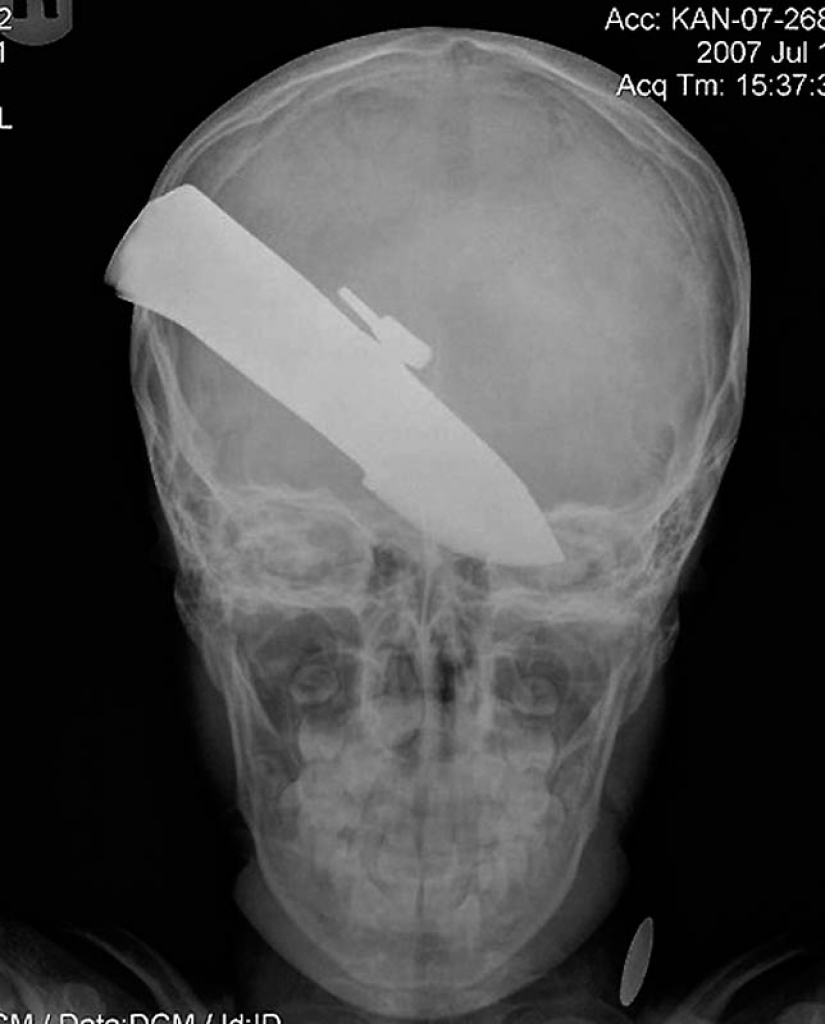

15. Cuchillo en la cabeza de niño de 10 años. El niño sobrevivió.

18. 12 centímetros de cuchillo en el cráneo de un adolescente.